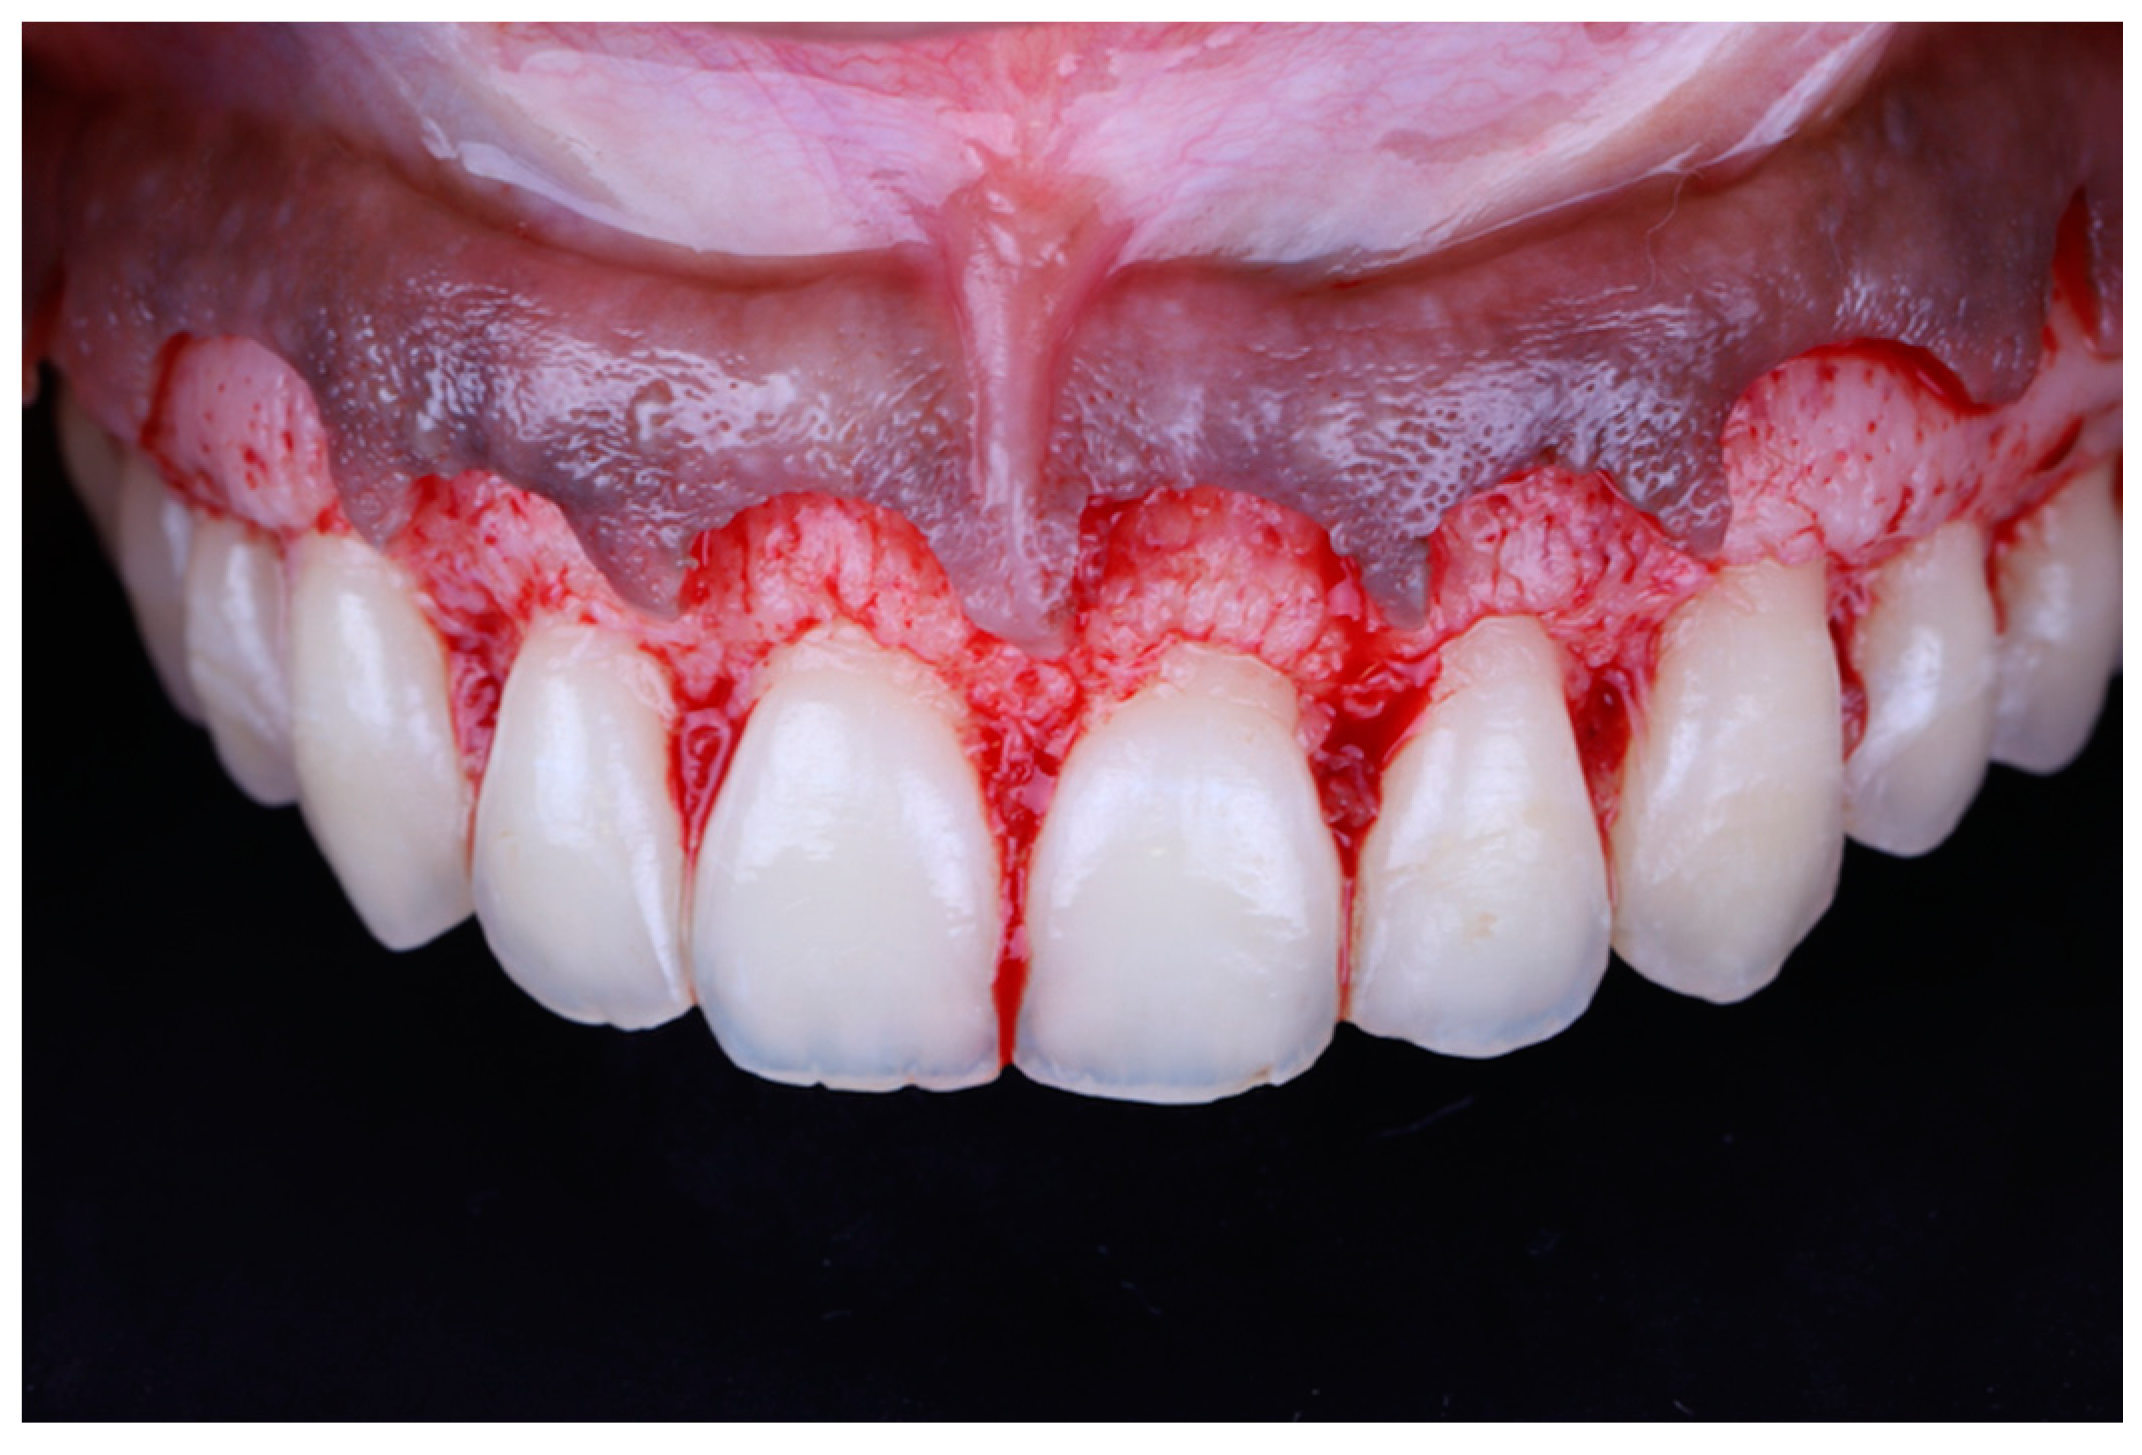

A full thickness mucoperiosteal flap was elevated past the mucogingival junction (Figure 7). The surgical guide was then placed again to determine the extent of osteoectomy needed (Figure 8), and the bone was marked with a round carbide bur. Using an end cutting carbide bur, osteoectomy was then performed; osteoplasty was performed after to remove buccal bone buttressing (Figure 9). The guide was then placed for a final check before internal vertical mattress sutures were placed using a monofilament non-resorbable material (5.0 Prolyne, Ethicon Inc, Somerville, NJ, USA) and hemostasis was ensured.

Figure 7.

Mucoperiosteal flap elevated.

Figure 8.

Surgical guide placed to determine level of osteoectomy.